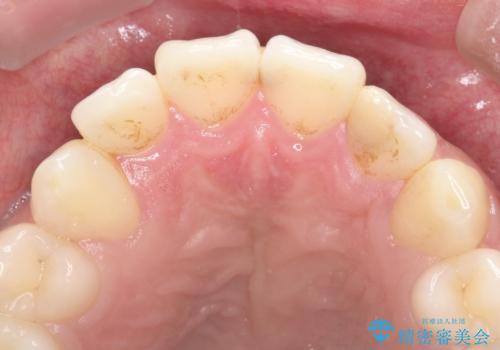

- 「前歯の歯の色が気になる」を主訴に来院された患者さんです。歯の大部分がプラスチックの材料で治療されていました。そこが劣化し変色していたためオールセラミッククラウンで治療を行いました。前歯の色を全体的に白くするために当院でオフィスホワイトニングも行いました。

左上2番の大部分がプラスチックの材料で治療されていました。そのプラスチックの材料が劣化して変色し虫歯になっている状態でした。なので古いプラスチックの材料を全て除去し、その下の虫歯を取った後、オールセラミッククラウンで治療を行いました。オールセラミッククラウンを装着する前に当院にてホワイトニングを行いました。